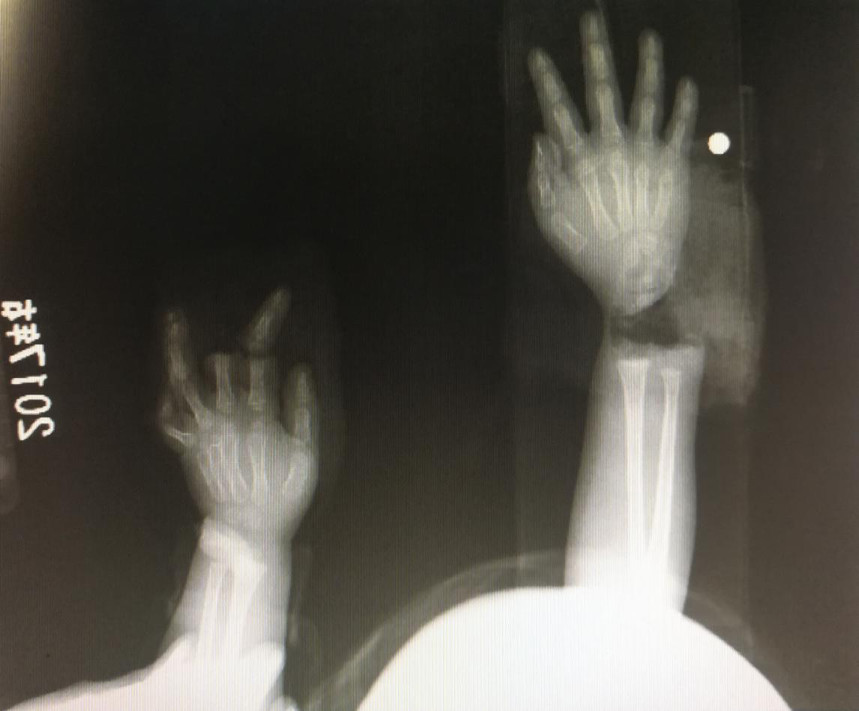

“急診在哪,急診在哪”,伴隨著一聲聲急促的問詢,一位年輕女士抱著渾身是血的小孩疾步前往急診室,懷里的小孩在疲憊與疼痛的交織下,時(shí)睡時(shí)醒。鑒于小孩的情況,急診醫(yī)生迅速安排給小孩拍了X光片,影像片結(jié)果顯示小孩左手手腕完全離斷,右手中、食指離斷,距離事發(fā)時(shí)間已經(jīng)3個(gè)多小時(shí),需盡快安排手術(shù)。

經(jīng)過長達(dá)5個(gè)多小時(shí)的手術(shù),小宇(化名)終于被送出了手術(shù)室,離斷的手腕和手指均已完成再植,但關(guān)于斷指的存活與否還需要經(jīng)過一個(gè)十天的觀察期。小宇的主治醫(yī)生是長沙年輪骨科醫(yī)院手足外科馬思成醫(yī)生,據(jù)馬醫(yī)生介紹,小宇受傷情況比較嚴(yán)重,失血過多,而且兩個(gè)手都存在完全離斷的情況,手術(shù)時(shí)安排了兩組醫(yī)生同時(shí)進(jìn)行,整個(gè)手術(shù)過程比較順利,目前小宇還處于觀察期。